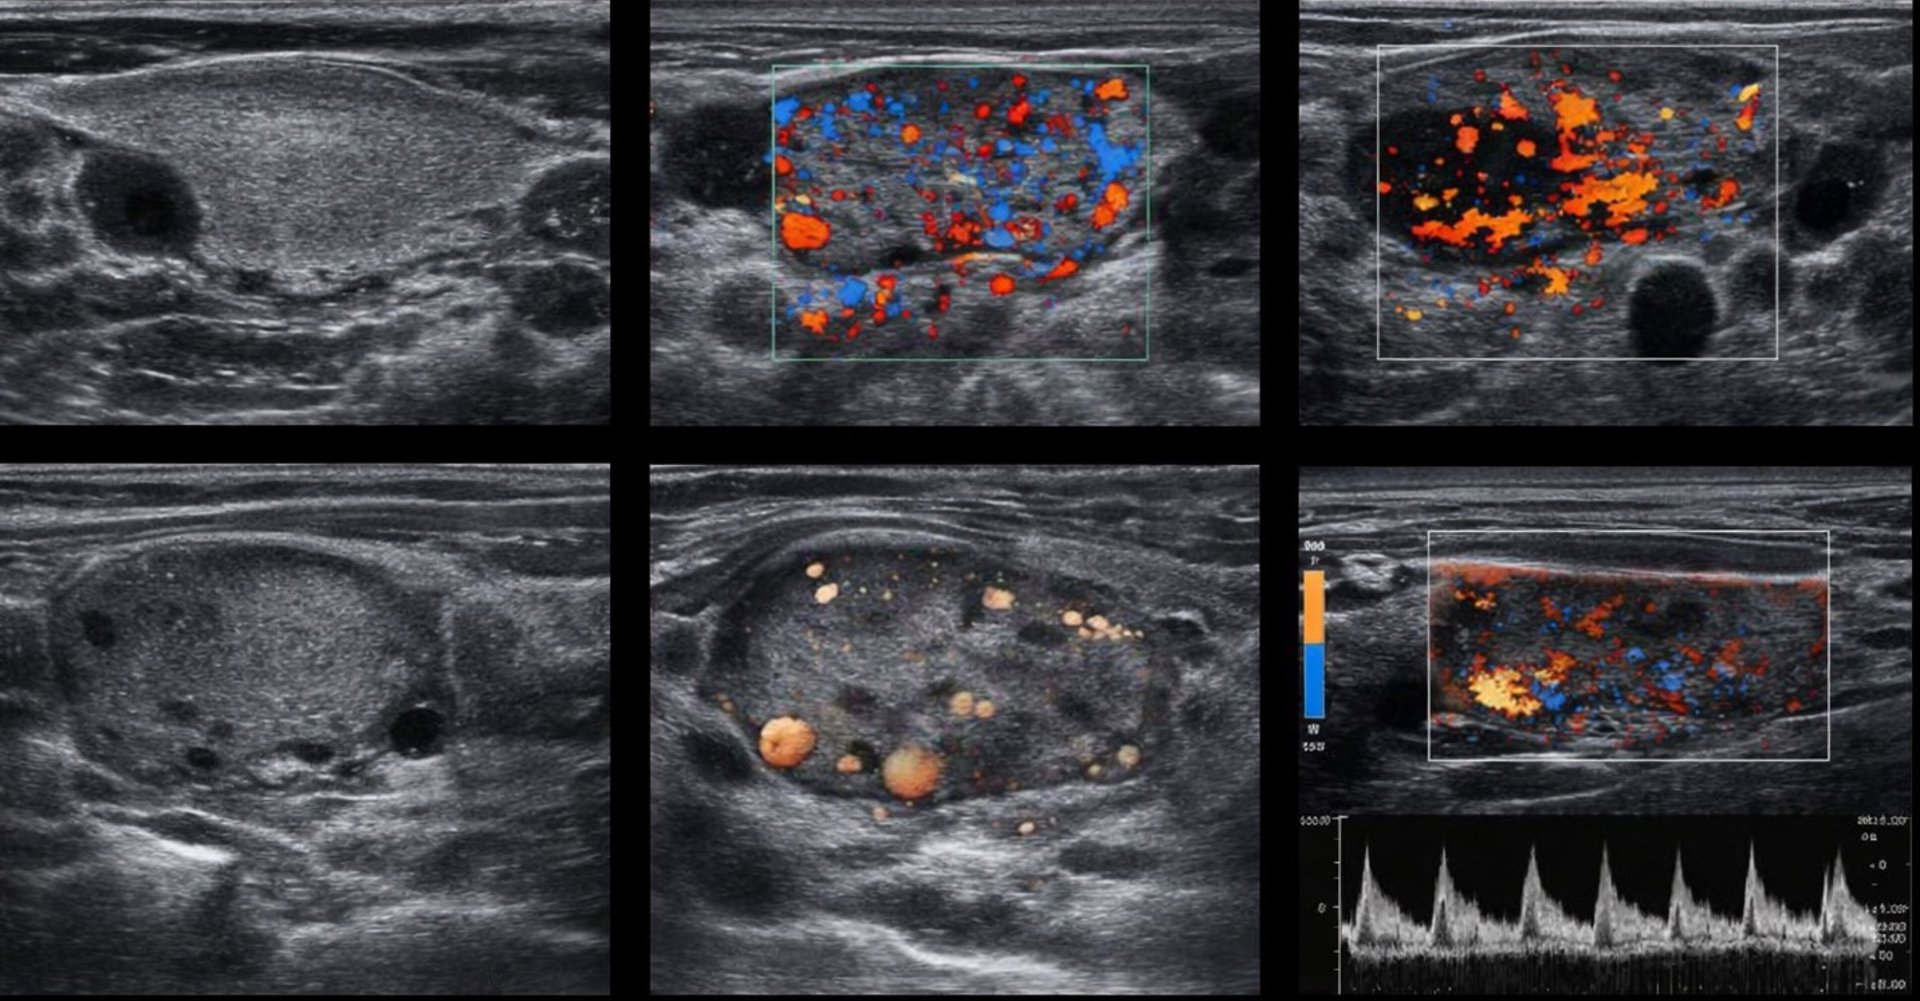

Practical, hands-on ultrasound instruction designed for endocrinologists who want immediate diagnostic clarity during a single patient visit. Learn focused thyroid and regional gland imaging using modern point-of-care systems with image quality comparable to high-end hospital platforms—without disrupting your workflow.

This hands-on ultrasound tutorial equips endocrinologists to perform focused thyroid and regional gland imaging at the point of care, improving diagnostic efficiency, patient experience, and practice sustainability.

Enables same-visit evaluation of thyroid nodules and regional gland pathology.

Modern POCUS systems provide resolution and Doppler capability comparable to hospital-based ultrasound.